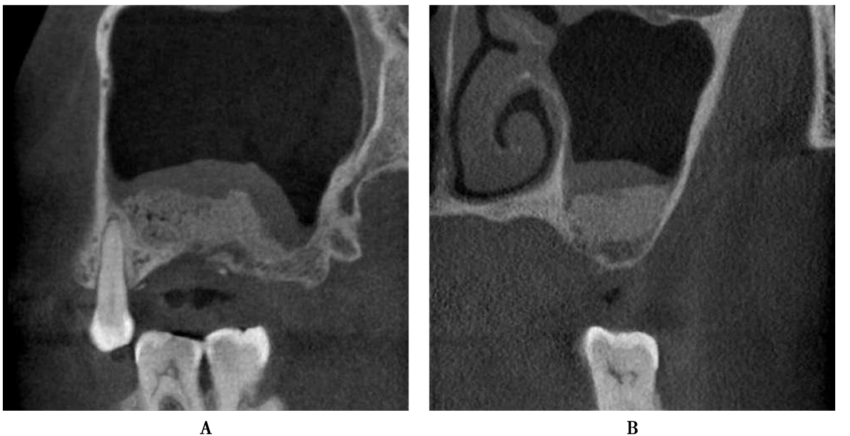

Stephen S.报道,使用机械磨头开窗,黏骨膜的穿孔率平均为30%,绝大多数穿孔发生在使用机械磨头和使用剥离器械进入上颌窦的时候,而不是在剥离的过程;而使用超声骨刀开窗:黏骨膜的穿孔率为7%。下面是一例上颌窦外提升手术过程中上颌窦黏膜发生穿通的病例。患者,女性,37岁,全身状况良好,要求种植牙修复。B5缺失,缺牙间隙大小合适,牙槽骨宽度理想(图11)。

术前CBCT显示缺牙区牙槽嵴顶到上颌窦底的最小高度约3mm,上颌窦底黏膜约1mm,上颌窦腔影像清澈,无炎症,侧壁厚度1~2mm(图12)。

图12 术前CBCTA.冠状面;B.矢状面